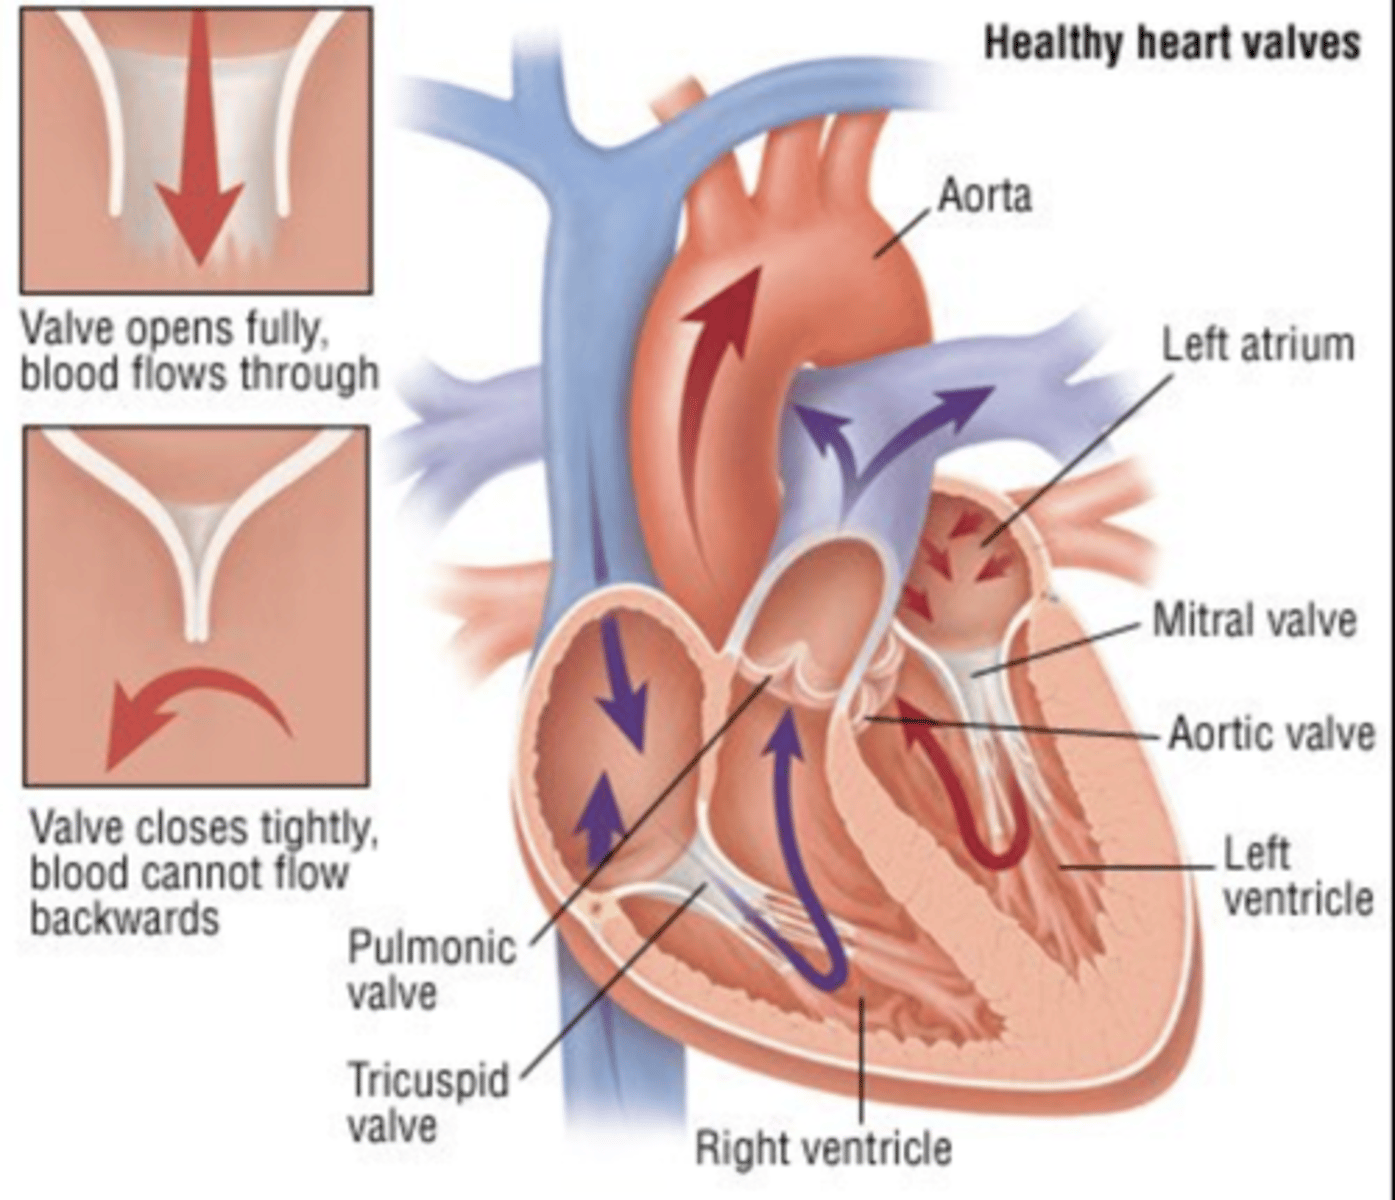

What valves are assuring the AV unidirectional flow?

Tricuspid (right)

Mitral or bicuspid (left)

How do the AV valves respond during the cardiac cycle?

AV valves open during diastole

AV valves close in systole

OPEN : ALLOW FLOW FROM ATRIA TO VENTRICLES

CLOSE : PREVENT BACKFLOW

How are the valves open in diastole?

AV valves are open,

Semilunar valves are closed

How are the valves open in systole?

AV valves are closed

Semilunar valves are open

SYSTEMIC CIRCULATION

flow of blood from body tissue to the heart and then from the heart back to body tissues

It carries oxygen and nutrients to the cells and picks up carbon dioxide and waste products

Describe in detail systemic circulation

From the left ventricle, oxygenated blood,

through the arteries,

to the capillaries in the tissues of the body.

From the tissue capillaries, the deoxygenated blood

returns through a system of veins to the right atrium of the heart. (superior and inferior cava veins)

PULMONARY CIRCULATION

Circulation of blood between the heart and the lungs

transports oxygen-poor blood from the right ventricle to the lungs,

where blood picks up a new oxygenated blood

Describe in detail pulmonary circulation

From the right ventricle poor oxygenated blood is impulsed

to the lungs, through the pulmonary artery

blood is oxygenated

returns to the left atria through the pulmonary veins

from where is the right atrium receiving the blood?

From the whole body

Right ventricle pumps blood to?

pulmonary artery

from where receives blood the left atrium?

pulmonary veins

Where pumps blood the left ventricle?

into the aorta